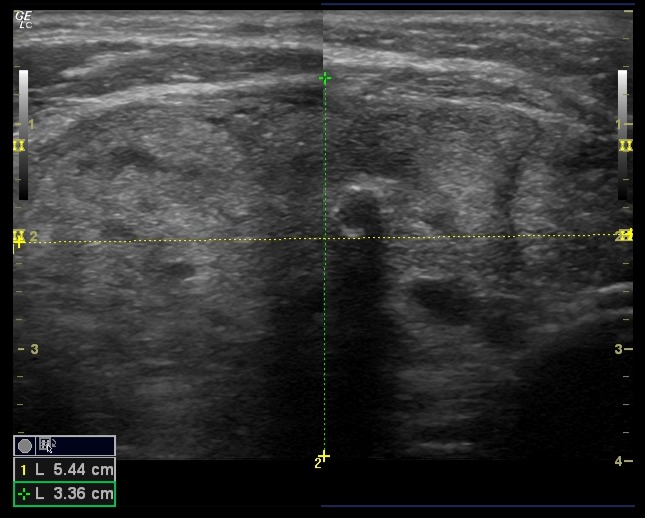

Ausencia de lóbulo izquierdo e istmo, en relación con cambios postquirúrgicos. Lóbulo tiroideo derecho aumentado, ocupado por conjunto de nódulos de aproximadamente 55 × 33 × 70 mm. Múltiples nódulos sólidos de ecogenicidad similar al parénquima; en Doppler se observa vascularización periférica. No se identifican adenopatías.

Se solicita ecografía preferente, cuyas conclusiones coinciden con las observadas: hallazgos compatibles con TI-RADS 3.